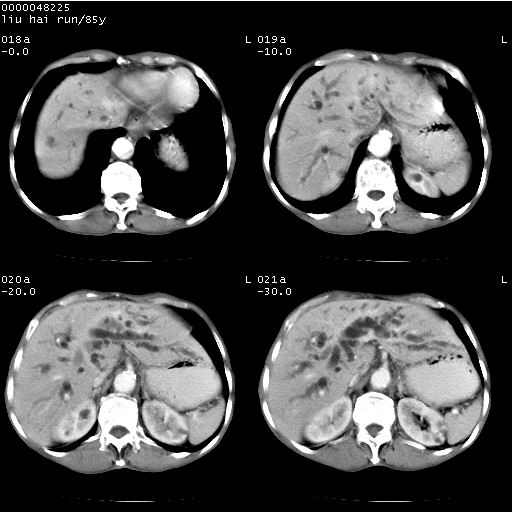

标题: CT13403:M,85Y。胆系低位梗阻。胰头占位? [打印本页]

标题: CT13403:M,85Y。胆系低位梗阻。胰头占位?

彩超示胰头实质欠均匀,胰管扩张。

有“双管征”,胆总管胰头段突然中断,考虑为胰头癌。

影像表现:壶腹部扩张胆管呈截断样改变,肝内外胆管重度扩张,胆囊增大,胰管亦明显扩张,呈不规则患珠样,胰体尾部略有萎缩,增强扫描后壶腹部低密度影轻度强化,与钩突分界不清。

ct诊断:胆管癌。鉴别诊断:胰腺癌,胰腺癌为少血供肿瘤,增强后强化不明显,静脉期及延时后与正常胰腺分界清晰。

胆总管下端突然截断,胰腺萎缩,胰管扩张,肝内外胆管扩张,考虑胆总管下端癌可能性大。不除外胰腺钩突占位。

1)胆系低位梗阻(肝内外胆管扩张、胰管扩张、胆囊增大);考虑为:胰头癌可能性大,不排除胆总管下端癌。2)双肾多发囊肿。